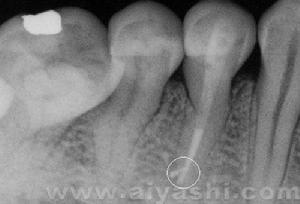

原尖根管治療術是當前根內外治療感染根管、牙髓病、根尖周病的主要方法,它是以外科手術來治療局部感染,

醫生在為患者做原尖治療